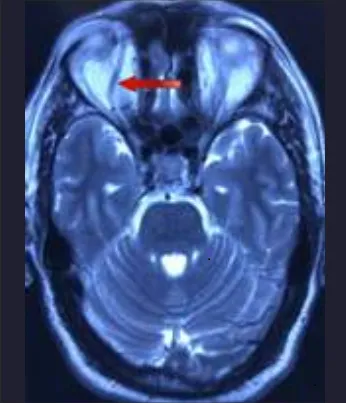

Clinical image showing chemosis, conjunctival injection, and slight proptosis of the right eye. Fundoscopy demonstrated papilledema and retinal venous engorgement of the right eye. Based on the above clinical presentation and ocular findings, a presumptive diagnosis of a CCF was made. A magnetic resonance imaging (MRI) of the brain was ordered which revealed marked enlargement of the right superior ophthalmic vein (SOV). The patient was then transferred to the department of neurovascular intervention for further management.

Brain MRI, axial view, demonstrating a dilated superior ophthalmic vein (red arrow)